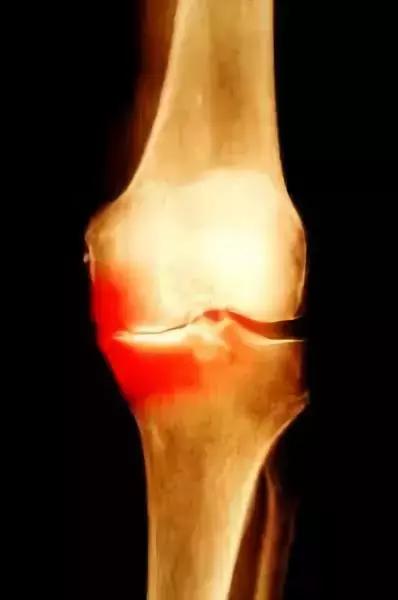

软骨的破坏是骨性关节炎的根本原因

晚期骨性关节炎的典型改变